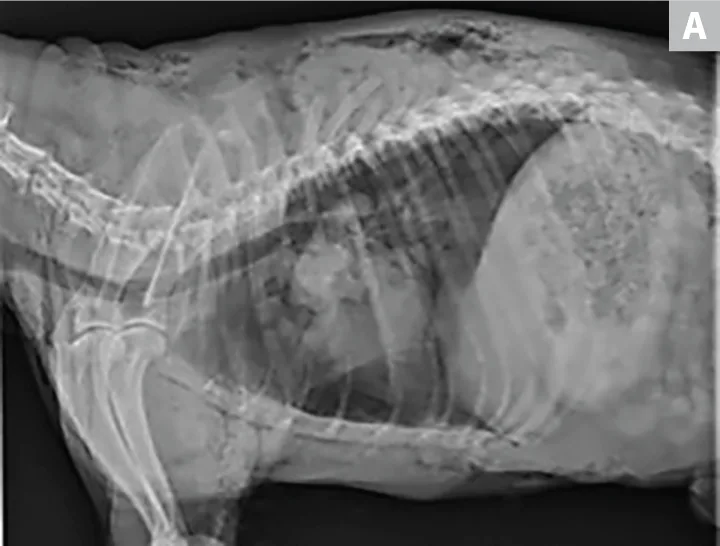

(A) Right lateral and (B) ventrodorsal radiographs of a 10-year-old neutered male schnauzer with flail chest from unknown trauma. The dog had severe subcutaneous emphysema, segmental fractions of the left 5th and 6th ribs, and a transverse fracture of the proximal left 7th rib. Left-sided pneumothorax and an alveolar pattern in the left cranial lung lobes were also noted.